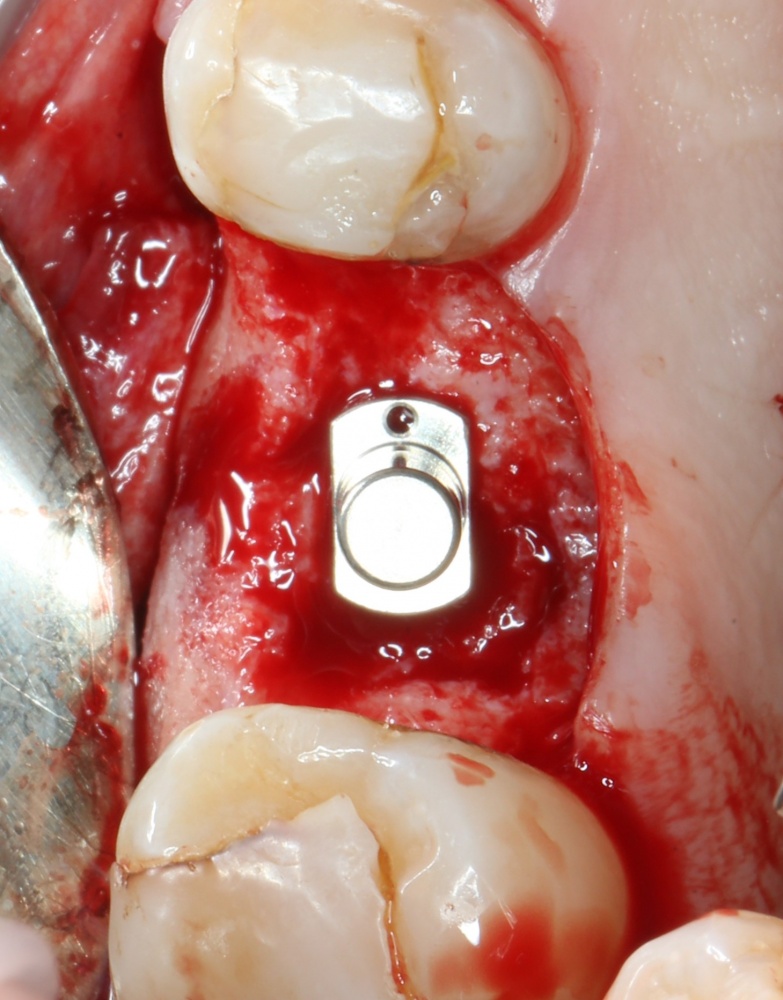

Кстати, комплект поставки не содержит ни заглушки, ни абатмента. А сам имплантат фиксируется на ключе простым заклиниванием платформы. Т. е. не слишком надёжно:

Если лунка подготовлена правильно, то имплантат проваливается в неё почти полностью:

Теперь заглушка. Упаковка заглушки еще более неудобная, чем упаковка имплантата: